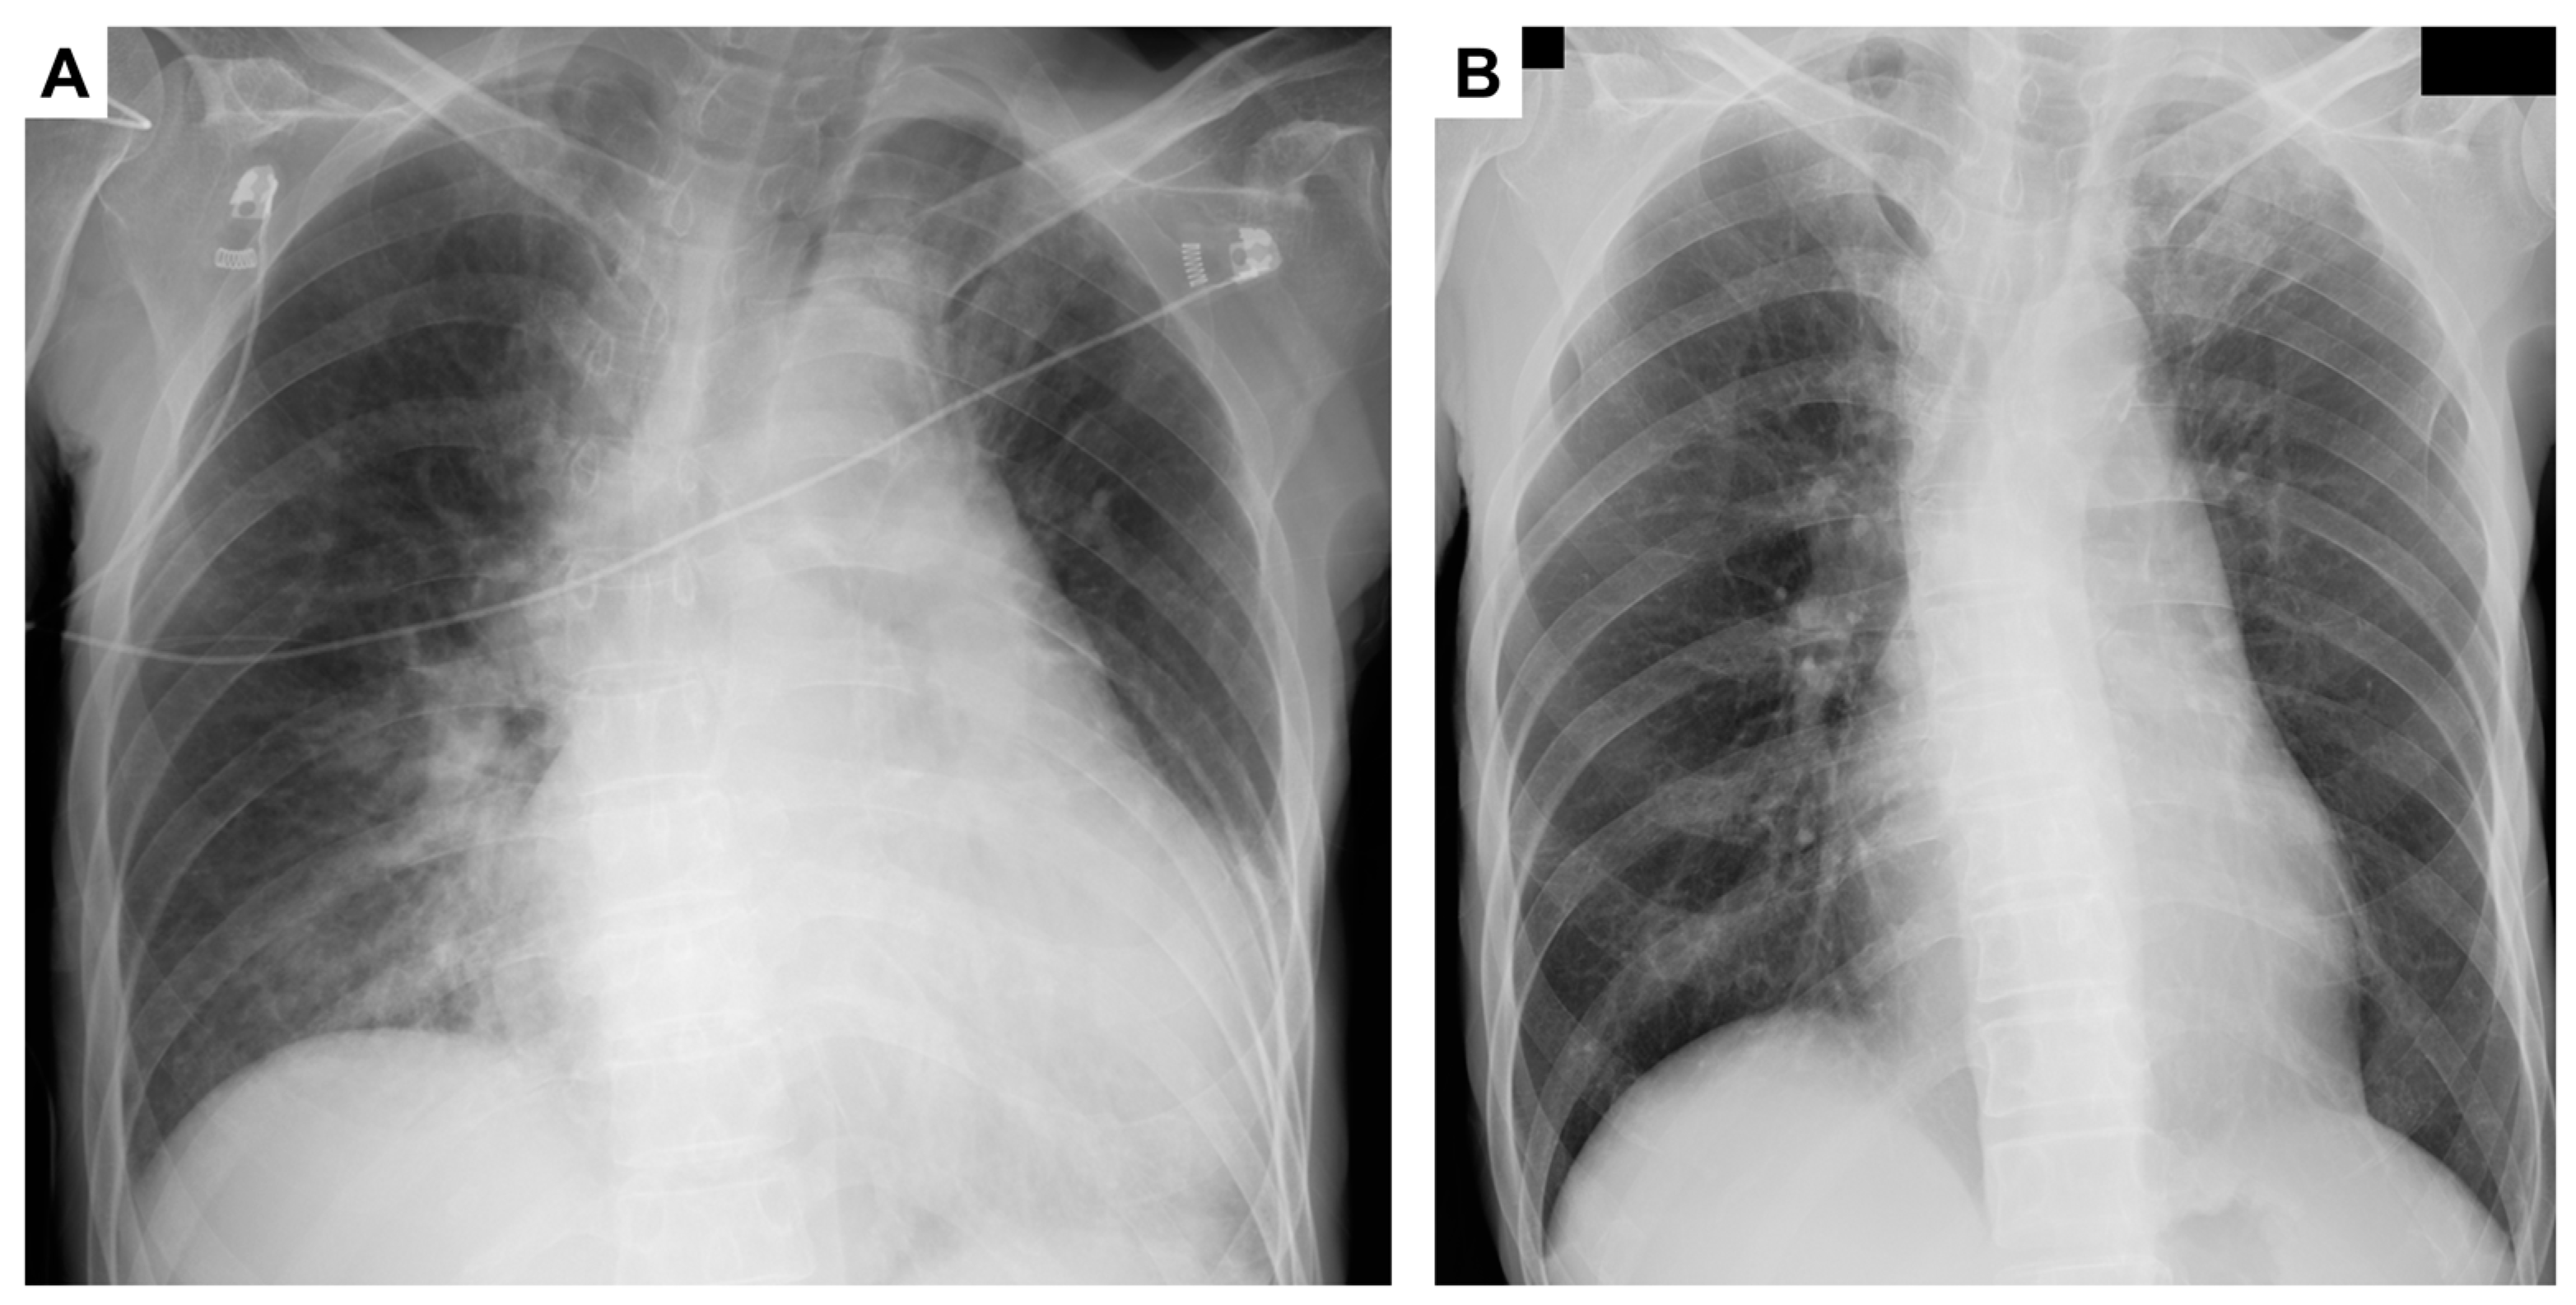

2. Case Presentation